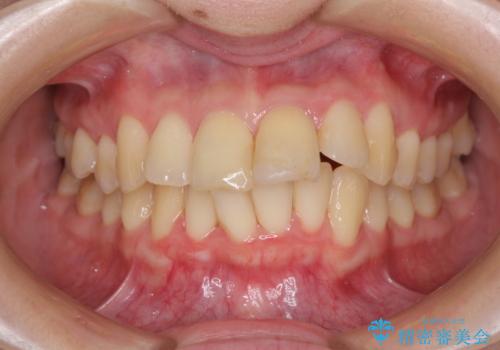

上下前歯のデコボコをきれいに インビザラインによる矯正治療

- 前歯の著しい叢生と前突感を気にして来院された患者様です。

叢生が強いため、事前に前歯をワイヤー矯正で速やかに叢生を解消し、その後はインビザラインにて矯正治療を行うこととしました。

ワイヤー矯正を併用したことで前歯の叢生を速やかに解消することができました。

一方口元の突出感を改善するために時間がかかり、2年超を要しましたが、満足のいく仕上がりとなりました。